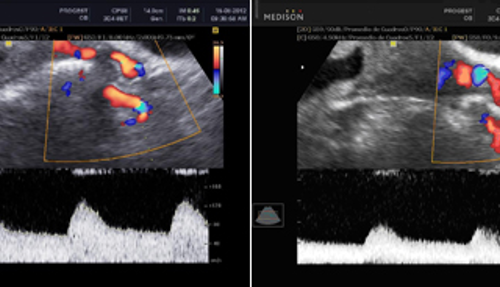

28 febrero, 2022Doppler Obstétrico Feto-Placentario

Evalúa en forma no invasiva el flujo de los vasos sanguíneos de la placenta, del feto, útero y del cordón umbilical, determina cómo está el flujo de sangre que le llega al feto, y por lo tanto el oxígeno y los nutrientes que recibe el bebé a través de la placenta. Si hay algún cambio en el flujo sanguíneo nos permitirá saber si hay necesidad de anticipar el parto. El uso del doppler reduce el número de muertes perinatales e intervenciones obstétricas innecesarias.

Este estudio nos permite predecir el riesgo que tiene la embarazada de presentar enfermedades como la preclamsia o restricción del crecimiento intrauterino en el feto, así como su seguimiento clínico.